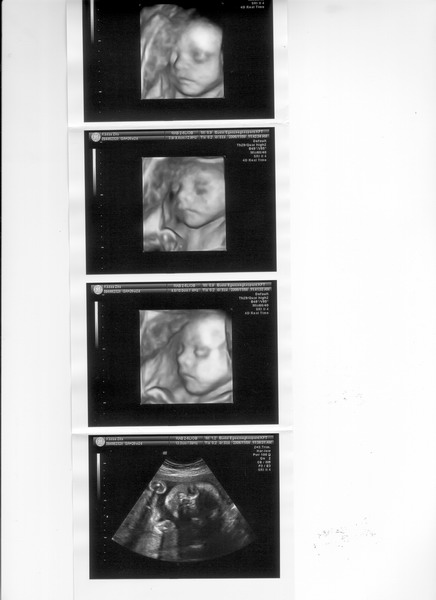

Mi is ma voltunk 3D-n. Nagyon edes volt Levi, viszont a kepek most sem tokeletesek. Ugy latszik velunk mindig ez van. De azert nekem nagyon tetszik! Mar tobb mint 2 kg-ra becsulik, 8.5 cm a feje

es meg van tobb mint egy honapja novogetni! A mostani adatok szerint is nagyobb a koranal, kb 33-34 hetes a meretei alapjan, ugyhogy ha igy halad akkor elobb kell jonnie, kulonben nem fogunk elferni.

En amugy is csak 38-ig tudok szamolni, ugyhogy egyatalan nem bannam ha picit elobb jonne vilagra.